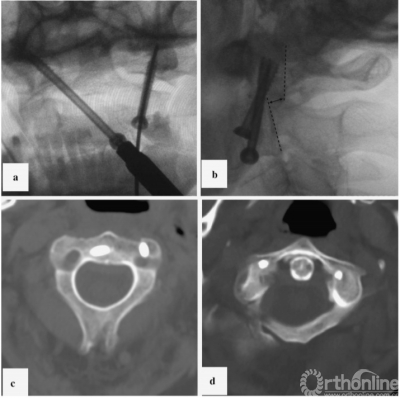

在使用Halo架的同时,将患者翻身至俯卧位,采用标准技术用直径4mm、长度40mm的空心皮质内固定螺钉进行左侧单侧经关节固定[7](图3 b)。x线图像及CT对照数据见图3c,d。在术后拆除Halo架。

图3病例1:固定时x线及对照CT扫描;a、使用对侧轨迹将克氏针置入右侧侧块;b、左侧单侧后路经关节固定;c、开口位x线;d、置钉后的三维CT扫描图片(轴位);螺钉位于寰椎两侧的侧块,左侧为双皮质;CT,计算机断层扫描

First, we used the Halo device for head fixation whilst the patient was in the supine position. One of the Halo pins was placed according to the location of the skull fracture and skin wound. For this reason, we fixed the Halo using only three pins, which allowed us to reposition appropriately and achieve immobilization during surgery. Reduction of the vertical atlantoaxial dislocation was performed using traction. Skin incision for contralateral screw insertion was planned using transoral radiography. A K-wire was attached according to the screw insertion trajectory. The intersection between the K-wire line and the medial edge of the sternocleidomastoid muscle indicated the midpoint of skin incision. The left anterior bar of the Halo device was temporally removed to facilitate approach performance during contralateral fixation. The left transcervical approach to the base of the C2 vertebra was performed through a 2cm skin incision. A port for the cannulated instrument was placed near the lower edge of C2, 5mm lateral from the midline. K-wire was inserted through the lower edge of C2 into the opposite lateral mass of the atlas under two-plane X-ray control (Fig.3a). This K-wire was used for bone tunnel drilling. A cannulated self-tapping cortical lag screw (4mm in diameter and 38mm in length) was inserted through this tunnel. The position of the screw head in the C2 vertebra facilitated fixation of the left lateral joint using the Reindl method; however, significant, bilateral thinning of the anterior lip of the C2 lateral mass (CT data; Fig.1,right) prevented us from using this technique. While using the Halo device, the patient was subsequently turned over into the prone position, and a left-sided unilateral transarticular fixation using a cannulated self tapping cortical lag screw (4mm in diameter and 40mm in length) was performed using the standard technique[7] (Fig.3b). Control X-ray images and CT data are provided in Fig.3c, d. Following surgery, the Halo device was removed.

Fig. 3 Case 1: X-ray images of the fixation stages and control CT scan. a K-wire insertion into the right lateral mass using a contralateral trajectory. b Left-sided unilateral posterior transarticular fixation. c Control X-ray in the transoral plane. d CT scan control after screw insertion (axial plane). Screws are located in the lateral masses of the atlas on both sides and are bicortical on the left side. CT computed tomography